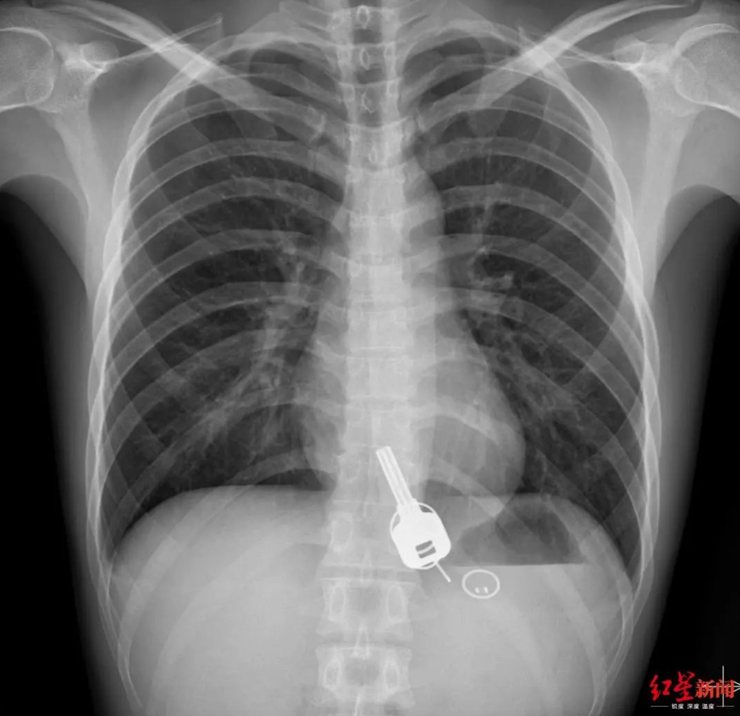

Þegar læknar settu hann í röntgen urðu þeir hissa því eitthvað sem líktist lykli var fast í vélinda hans. Þeir spurðu hann um hann og hann játaði að hafa týnt lyklunum sínum kvöldið áður en gat enga skýringu gefið á því af hverju þeir væru þarna niður komnir.

Málið var snúið, því ef Chang hefði verið látinn melta lykilinn á sama hátt og fæðu hefði það getað rifið einhver innyfli á hol. Að toga hann upp gat líka rifið gat á vélindað. Þriðji kosturinn, og sá sem kom helst til greina var skurðaðgerð.

Eftir margar tilraunir starfsfólk sem einnig glímdi við manneklu á spítalanum vegna frídags, var Chang gefin kæruleysissprauta þannig að það slaknaði á vöðvunum. Þannig var hægt að toga lykilinn út ásamt plastlykli (korti) upp úr vélindanu.